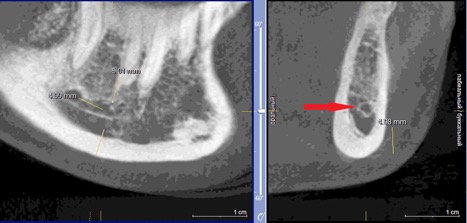

При измерении расстояния от резцовой петли до вестибулярной стенки нижней челюсти и её топографии в области правила «трёх пятёрок», выделено три положения канала, в котором проходит резцовая петля: канал прилежит, т.е. стенка канала образована кортикальной частью (рис 3), касается, т.е. имеет одну общую точку (рис 4) и не имеет общих точек.

Рисунок 3. КЛКТ Сагиттальныи и коронарныи реформаты переднего отдела нижнеи челюсти..jpg

Рисунок 3. КЛКТ Сагиттальный и коронарный реформаты переднего отдела нижней челюсти.

Стенка канала образована кортикальной частью кости.

Красная стрелка – «резцовая петля».

Красный пунктир – канал проходит в проекции участка правила «трёх пятёрок».

Рисунок 4. КЛКТ Сагиттальныи и коронарныи реформаты переднего отдела нижнеи челюсти..jpg

Рисунок 4. КЛКТ Сагиттальный и коронарный реформаты переднего отдела нижней челюсти.

Канал соприкасается с кортикальной частью кости (красная стрелка – резцовая петля).